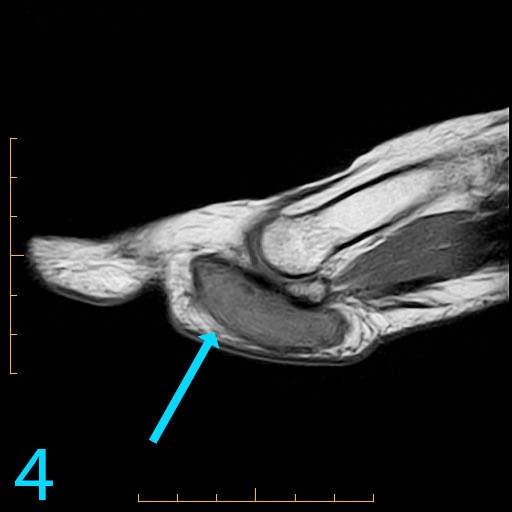

This 18-year-old female presents with a palpable soft tissue mass subjacent to the first metatarsophalangeal (MP) joint that she has noticed for 1-2 months. It is painful with shoes and ambulation, and you are evaluating her for a soft tissue tumor. What is the cause of her problem, and what pertinent negatives must you notice?

This patient has a so-called "pressure lesion" due to ambulation, with associated adventitial bursa/pseudobursa formation within. It is a chronic process. This is manifested as a large, ovoid mass-like structure within the subcutaneous soft tissues along the plantar aspect of the first MP joint and sesamoid bones (arrow). It is well-circumscribed and demonstrates a mildly lobulated configuration. There is peripheral signal hypointensity indicating a rim or rind of fibrosis, and there is intermediate to high T2 signal centrally, suggesting a component of complex fluid. The major differential diagnosis is fibroma of tendon sheath. This is a counterintuitive diagnosis as fibrous lesions are typically dark on all pulsing sequences. But, fluid signal from the tendon sheath may be found in this specific fibrous tumor. So, fibromas of tendon sheath are typically hyperintense centrally.

While the lobulation of the lesion medially is reminiscent of plantar fibromatosis, the constellation of findings remains most compatible with a giant pressure lesion. Fibromatosis (non-aggressive type) occurs more proximally in the middle aponeurotic cord of the plantar fascia. The findings are not suspicious of an aggressive neoplastic lesion (based on location and concentric shape), and you can also rule out MP joint capsulitis and Morton's neuroma because of location. You should always rule out plantar plate tear along the second MP joint on thin section sagittals if you have a large pressure lesion under the second metatarsal head. For more case review, visit MRI Online.